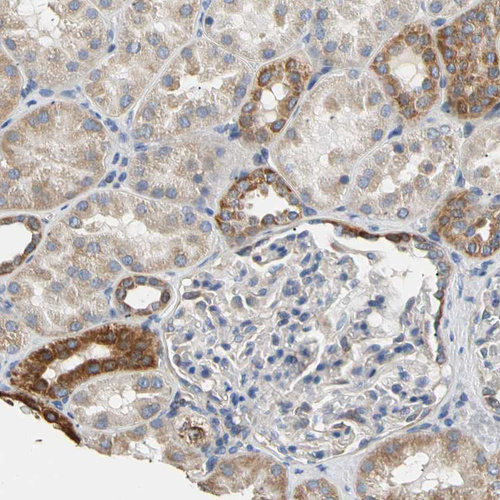

Immunohistochemistry analysis in human rectum and pancreas tissues using HPA008214 antibody. Corresponding PLGRKT RNA-seq data are presented for the same tissues.